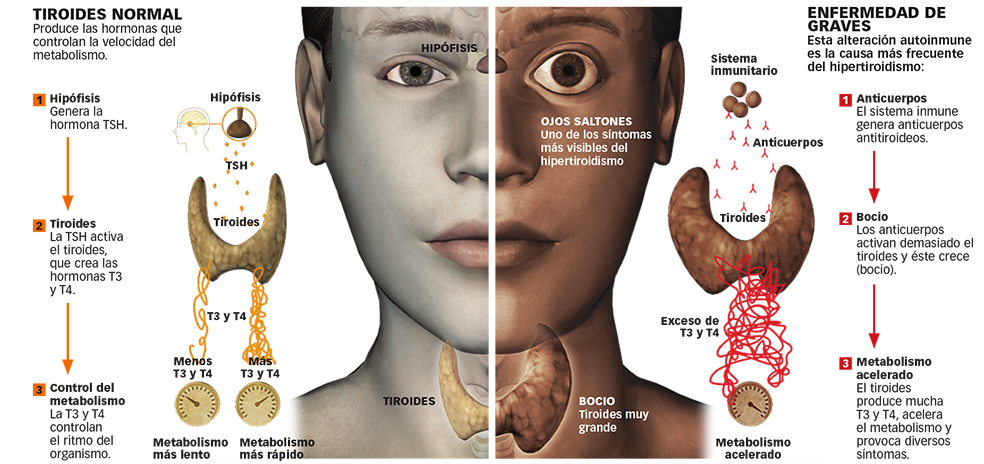

Esta pequeña glándula con forma de mariposa es el centro de control del metabolismo, su director de orquesta. Su función es sintetizar, almacenar y liberar hormonas tiroideas, que son las encargadas de asegurar que los tejidos y órganos de nuestro cuerpo funcionan correctamente y a la velocidad adecuada. «Regulan casi todas las funciones: cardiaca, muscular, hepática…; por eso, una mala salud tiroidea va a condicionar síntomas de todo tipo», afirma la doctora Elena Navarro, especialista en Endocrinología y Nutrición en el Hospital Universitario Virgen del Rocío, de Sevilla, y coordinadora del Área de Tiroides de la Sociedad Española de Endocrinología y Nutrición (SEEN).

En estos momentos se considera que un 10 por ciento de la población española padece una enfermedad del tiroides (aunque se estima que una gran parte no ha sido diagnosticada). En la mayoría de los casos –un 91 por ciento–, esta disfunción se debe a que su actividad ha disminuido, lo que provoca una cantidad insuficiente de hormona; es lo que conocemos como hipotiroidismo.

El 9 por ciento restante se debe a la situación contraria: el tiroides está demasiado activo y produce demasiada hormona. Es el hipertiroidismo. Ambas son las disfunciones más comunes, muy por encima de los casos de bocio o de cáncer de tiroides. Y todas ellas son, por causas que no terminan de estar claras, mucho más prevalentes en mujeres.